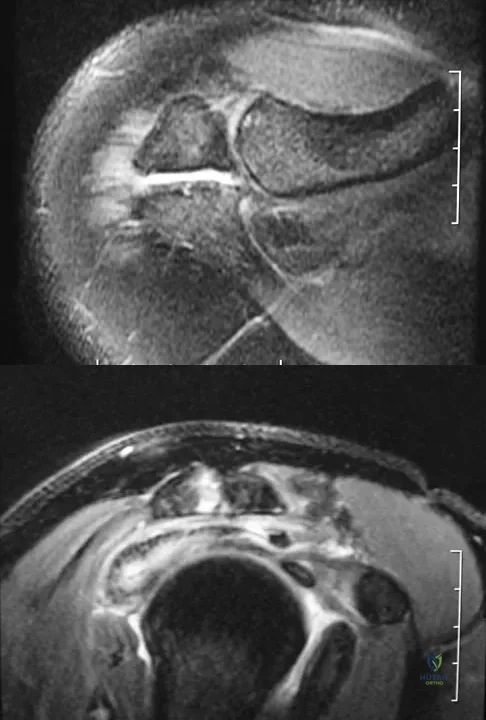

A 28-year-old man has left knee pain after a snow skiing accident. The MRI scan shown in Figure 47 reveals which of the following?

Figures 34a and 34b show the axial and sagittal MRI scans of a 36-year-old man who reports the insidious onset of pain in the right shoulder. What is the most appropriate description of the acromial morphology?